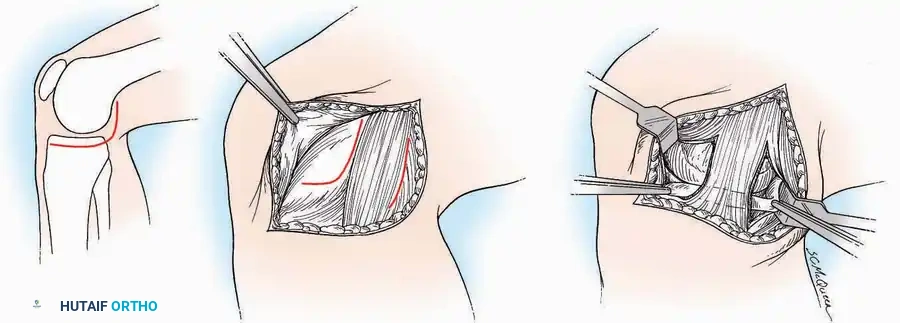

Lateral Approach (Extensile Lateral)

This is the workhorse approach for open reduction and internal fixation (ORIF) of displaced intra-articular calcaneal fractures.

Indications: ORIF of calcaneus fractures, lateral wall exostectomy, subtalar arthrodesis.

Positioning: Lateral decubitus with the operative leg up, or supine with a large bump under the ipsilateral hip to internally rotate the leg.

Surgical Technique:

* Incision: Begin the incision on the lateral margin of the Achilles tendon near its insertion. Extend it distally to a point 4 cm inferior and 2.5 cm anterior to the lateral malleolus. (For trauma, a classic L-shaped extensile incision is often used, dropping straight down anterior to the Achilles, then curving gently toward the base of the 5th metatarsal).

* Superficial Dissection: Divide the superficial and deep fasciae. It is imperative to create a "full-thickness" flap containing skin, subcutaneous fat, and periosteum to prevent flap necrosis.

* Nerve Protection: The sural nerve crosses the proximal and distal limbs of this approach. It must be identified and protected within the anterior flap.

* Deep Dissection: Isolate the peroneal tendons (longus and brevis). Incise and elevate the periosteum below the tendons to expose the lateral wall of the calcaneus.

* Tendon Management: If severe deformity or infection is present, the peroneal tendons may be divided via Z-plasty and repaired at the conclusion of the case, though this is rarely necessary in modern fracture care.